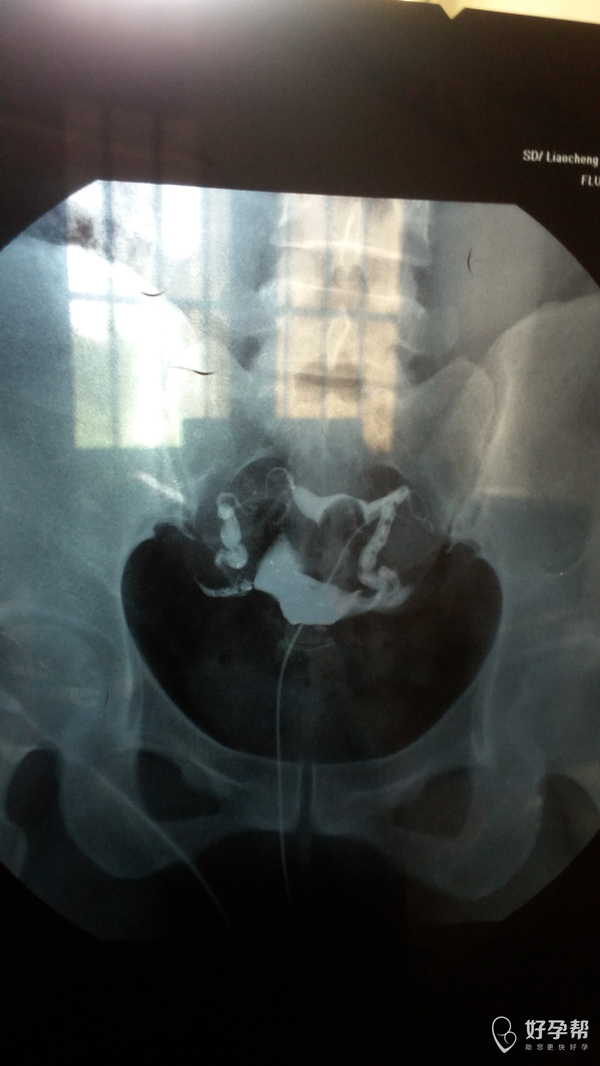

您好,双侧输卵管通畅的,但是双侧输卵管远端增粗,盆腔弥散不好,不排除盆腔粘连。